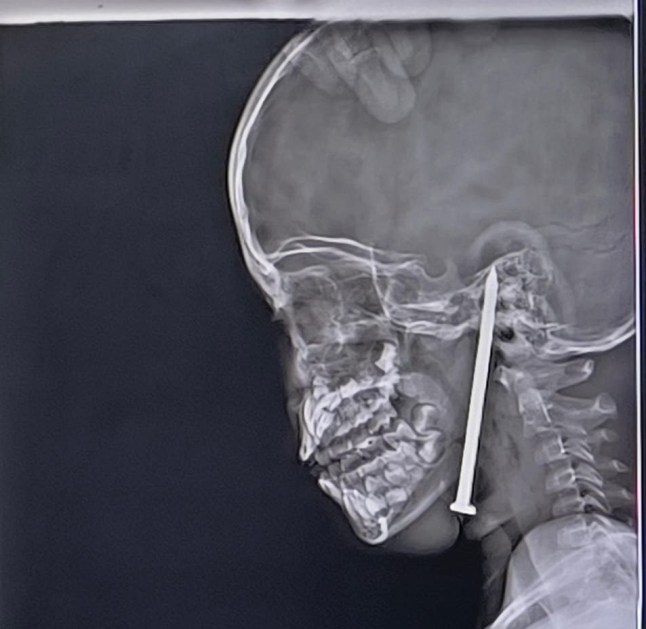

X-ray images showed the nail lodged inside the base of the girl’s head (Picture: SWNS)

It had pierced her neck,passing below the jaw and through the palate into the cranial cavity,where it partially entered her brain.

The nail had travelled through the neck and palate (Picture: SWNS)